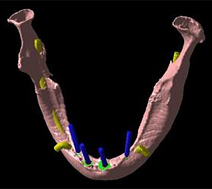

(2)撮影したCT画像を専門の画像解析センターをへて、CTデータ3D立体構築画像変換検査に移します

インプラント断面

![]() |

意図的傾斜埋入をインプラント断面で診断可能 |

骨質のカラー表示

ハンスフィールドユニット(CT値)によって骨質が診断可能 |

模型の合成

金属アーティファクトのない3D画像の実現 |

骨移植シミュレーション

骨採取する骨量を測定可能 |